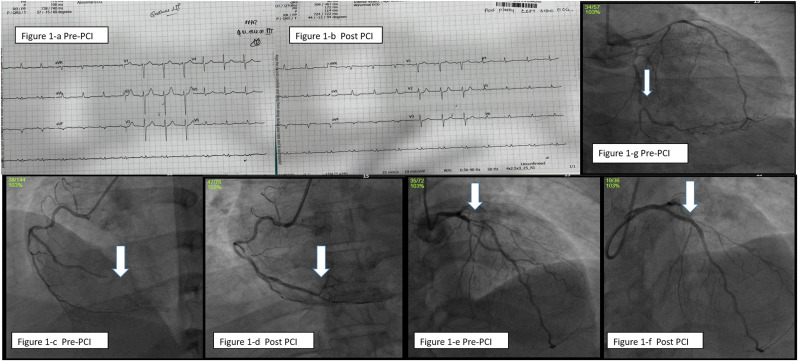

Case-1: A 46-year-old male patient reported with difficulty in breathing and acute persistent cough as chief complaints. He was a known diabetic since 10 years and hypertensive for past 5 years. History revealed, he had received second dose of COVID-19 vaccine (COVISHIELD) 12 days before. He was hemodynamically stable. His Troponin-T tested positive and level of COVID antibody was 100. His platelet count was 518 10³/mm³ with high sugar levels of fasting blood sugar (FBS) of 184 mg% and post prandial blood sugar (PPBS) of 386 mg%. Computerized Tomography(CT) chest was suggestive of pulmonary edema. Electrocardiography (ECG) showed Sinus rhythm (SR), evolved infero-posterior wall myocardial infarction (IPWMI) (Fig. 1 -a, 1-b). Echocardiography (Echo) revealed mild left ventricular hypertrophy (LVH), regional wall motion abnormality (RWMA) involving infero-posterolateral wall with left ventricular ejection fraction(LVEF)of 55%. He was loaded with anti-platelets, statins and was lysed with Reteplase in a nearby clinic. After overnight stabilization, he arrived at our hospital and underwent coronary angiogram (CAG), which showed triple vessel disease (TVD) (severe disease of left anterior descending artery (LAD), distal left circumflex(dLCX) and 100% occlusion of distal right coronary artery (dRCA)) (Fig. 1-c,1-e,1-g). Adhoc percutaneous coronary intervention (PCI) to culprit RCA and proximal LAD (Fig. 1-d,1-f) were done with 2.0 × 30mm, 2.5 × 26mm RESOLUTE ONYX stents respectively and was discharged after 2 days.

Figure 1.

a: Electrocardiogram (ECG) showing infero-posterior wall myocardial infarction (IPWMI) prior to Percutaneous coronary intervention (PCI)

Figure 1-b: ECG showing evolved infero-posterior wall myocardial infarction (IPWMI) after PCI

Figure 1-c: Right coronary artery angiogram (RCA) showing 100% occlusion of distal RCA

Figure 1-d: RCA angiogram (RCA) showing well-opened up RCA after stenting.

Figure 1-e: Left coronary artery angiogram (LCA) showing severe disease of proximal Left anterior descending artery(LAD)

Figure 1-f: LCA angiogram showing well opened up proximal Left anterior descending artery(LAD) after stenting.

Figure 1-g: LCA angiogram showing severe disease of distal left circumflex artery(dLCX)